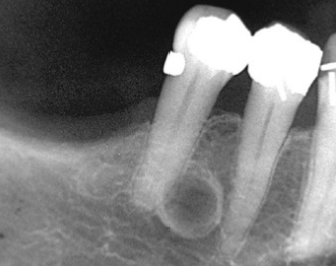

Describe this Residual Cyst

Extraction site at periapical level

Above IAN Canal

Lucent

Circular, oval

Defined

Corticated unless infected

Displacement, Resorption (effect on adjacent structures)

What is this dental anomaly?

Residual Cyst